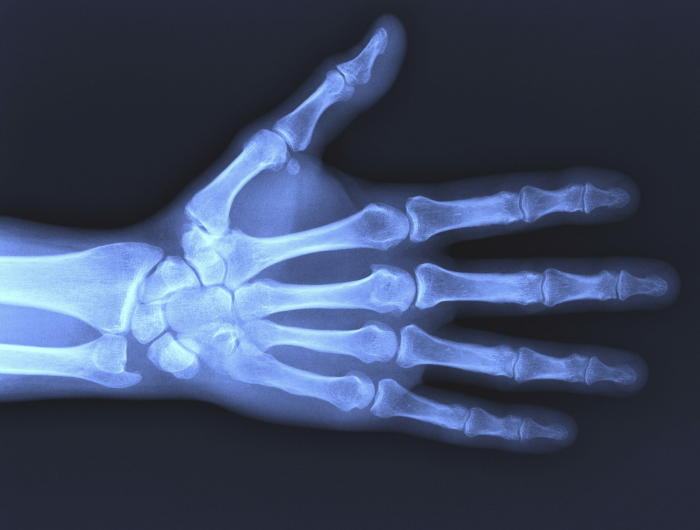

La radiología es una rama de la medicina que utiliza la tecnología imagenológica para diagnosticar y tratar una enfermedad. Se puede dividir en dos áreas diferentes: radiología diagnóstica y radiología intervencionista. Los médicos que se especializan en radiología se denominan radiólogos.

Estudios que realizamos

Se realizan, entre otros, los siguientes estudios radiológicos no contrastados (de frente/perfil/oblicuo/parado o acostado):